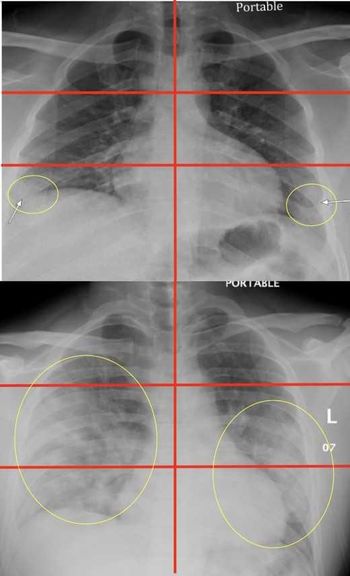

Racial and ethnic minority patients show more severe cases on chest X-ray, fueled by socioeconomic factors.

X-ray classification system developed at Mount Sinai can help identify patients who will most likely need hospitalization and intubation.